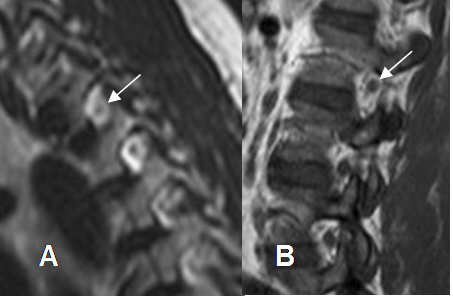

Fig 26. Emergencia de raíces.

TAC axial lumbar. Emergencia de la raíz (Flecha delgada). GD: ganglio de la raíz dorsal. (Flecha gruesa) y saco dural (Punta de flecha).